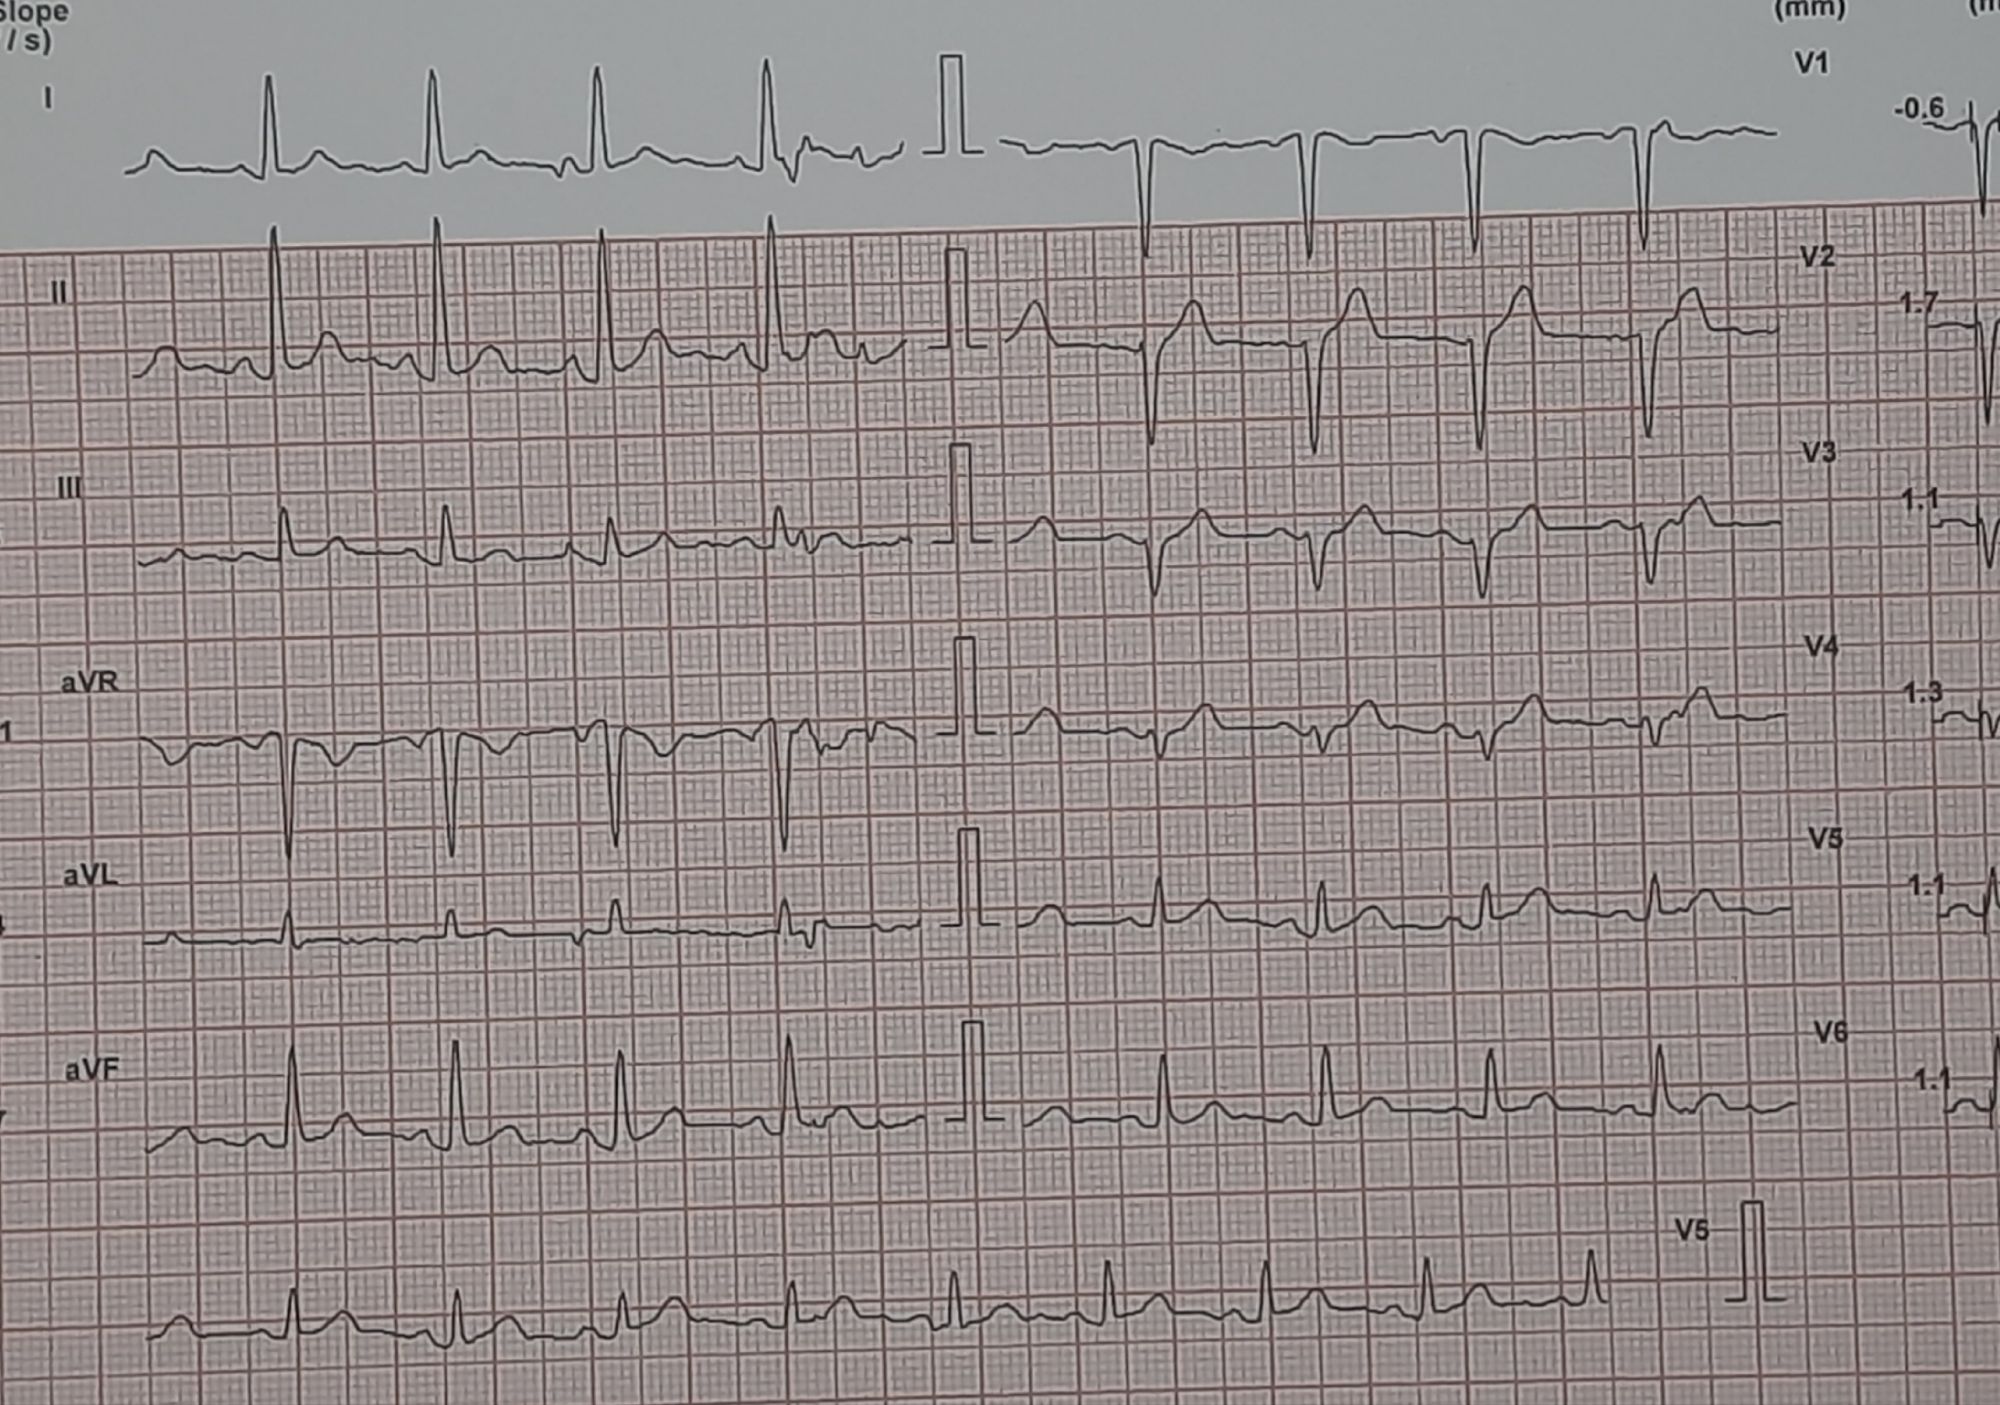

Here is a middle-aged man who went for an annual health check and ended up with this TMT. His exercise capacity was good at 11 METs, stopped at early stage 4 standard Bruce. He was asymptomatic, and every other parameter was normal.

Images: Resting, Peak, severe positive response, in lead V5 and V6. Every cardiologist advised some form of CAG. Opinions were so diverse, ranging between silent left main, tight proximal LAD to innocuous false positive.

What is your inference ? The patient seeked by advice It was indeed an academic stress test. There is a frightening ST depression I said. yes the rest is very likely to be false positive but I don’t have the courage to commit so. Mostly, you can’t escape from a coronary angiogram” . Next option is CT angiogram, Thallium or dobutamine stress.

It was indeed an academic stress test. There is a frightening ST depression . Very difficult to Ignore. May be, it could be false positive but I don’t have the courage to commit so. Mostly, you can’t escape from a coronary angiogram” .Other options are  CT angiogram, Thallium or dobutamine stress.